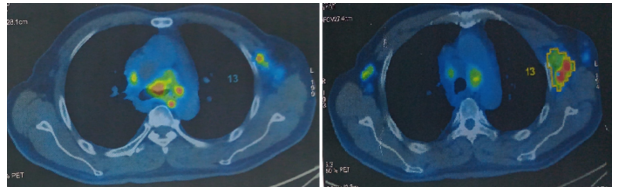

Hình 3: Hình ảnh hạch bất thường trung thất và hạch nách

Hình 4: Hình ảnh các hạch ổ bụng tăng chuyển hoá FDG

- Hình ảnh nhiều hạch trung thất ở trước các mạch máu lớn, cạnh khí quản, dưới quai, trước và dưới carina, hạch lớn nhất kích thước 25x18mm, tăng chuyển hoá FDG.

- Hình ảnh nhiều hạch rốn phổi, hạch lớn kích thước 15x18mm, tăng chuyển hoá FDG.

- Hình ảnh nhiều hạch hố nách 2 bên, hạch lớn kích thước 21x40mm, tăng chuyển hoá FDG.